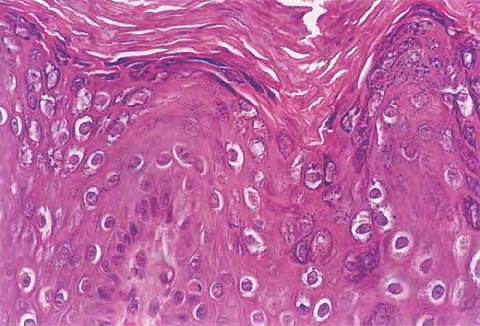

Read MoreVerruca palmoplantaris = الثؤلول الراحي الاخمصي